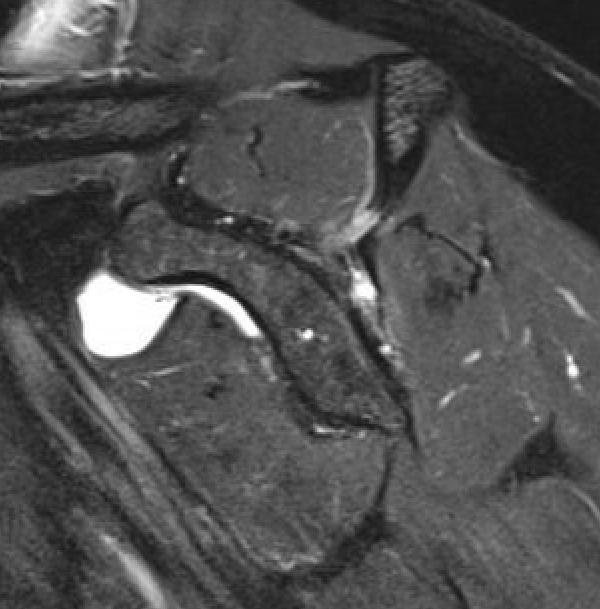

MRI

Measure tear in the coronal and sagittal plane

Massive rotator cuff tear of the supraspinatus and infraspinatus tendon - retracted to glenoid

Examples of rotator cuff tears that are likeley irreparable